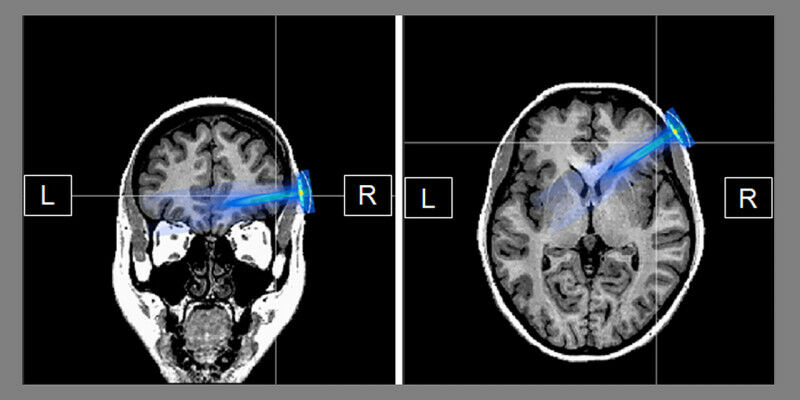

The TUS technique has the potential to safely target deeper areas of the brain even at low energies. The elliptical blue area shows its area of influence in the current study, the right prefrontal cortex. This area is associated with brain regions that produce the EEG parameter of the mid-frontal theta frequency, which is central to the study and could be successfully influenced by ultrasound. (Image: Philipp Ziebell / Johannes Rodrigues / André Forster)

The TUS technique has the potential to safely target deeper areas of the brain even at low energies. The elliptical blue area shows its area of influence in the current study, the right prefrontal cortex. This area is associated with brain regions that produce the EEG parameter of the mid-frontal theta frequency, which is central to the study and could be successfully influenced by ultrasound. (Image: Philipp Ziebell / Johannes Rodrigues / André Forster) - Psychologists at the University of Würzburg have investigated the extent to which neuromodulation of the brain with ultrasound waves influences people's behavior. The results can also be used as a basis for therapeutic purposes. When a new opportunity opens up for people, there are some who tend to take the pessimistic view: "It's no good anyway!". They may initially accept it, but in the long term they are constantly in a state of inner conflict.